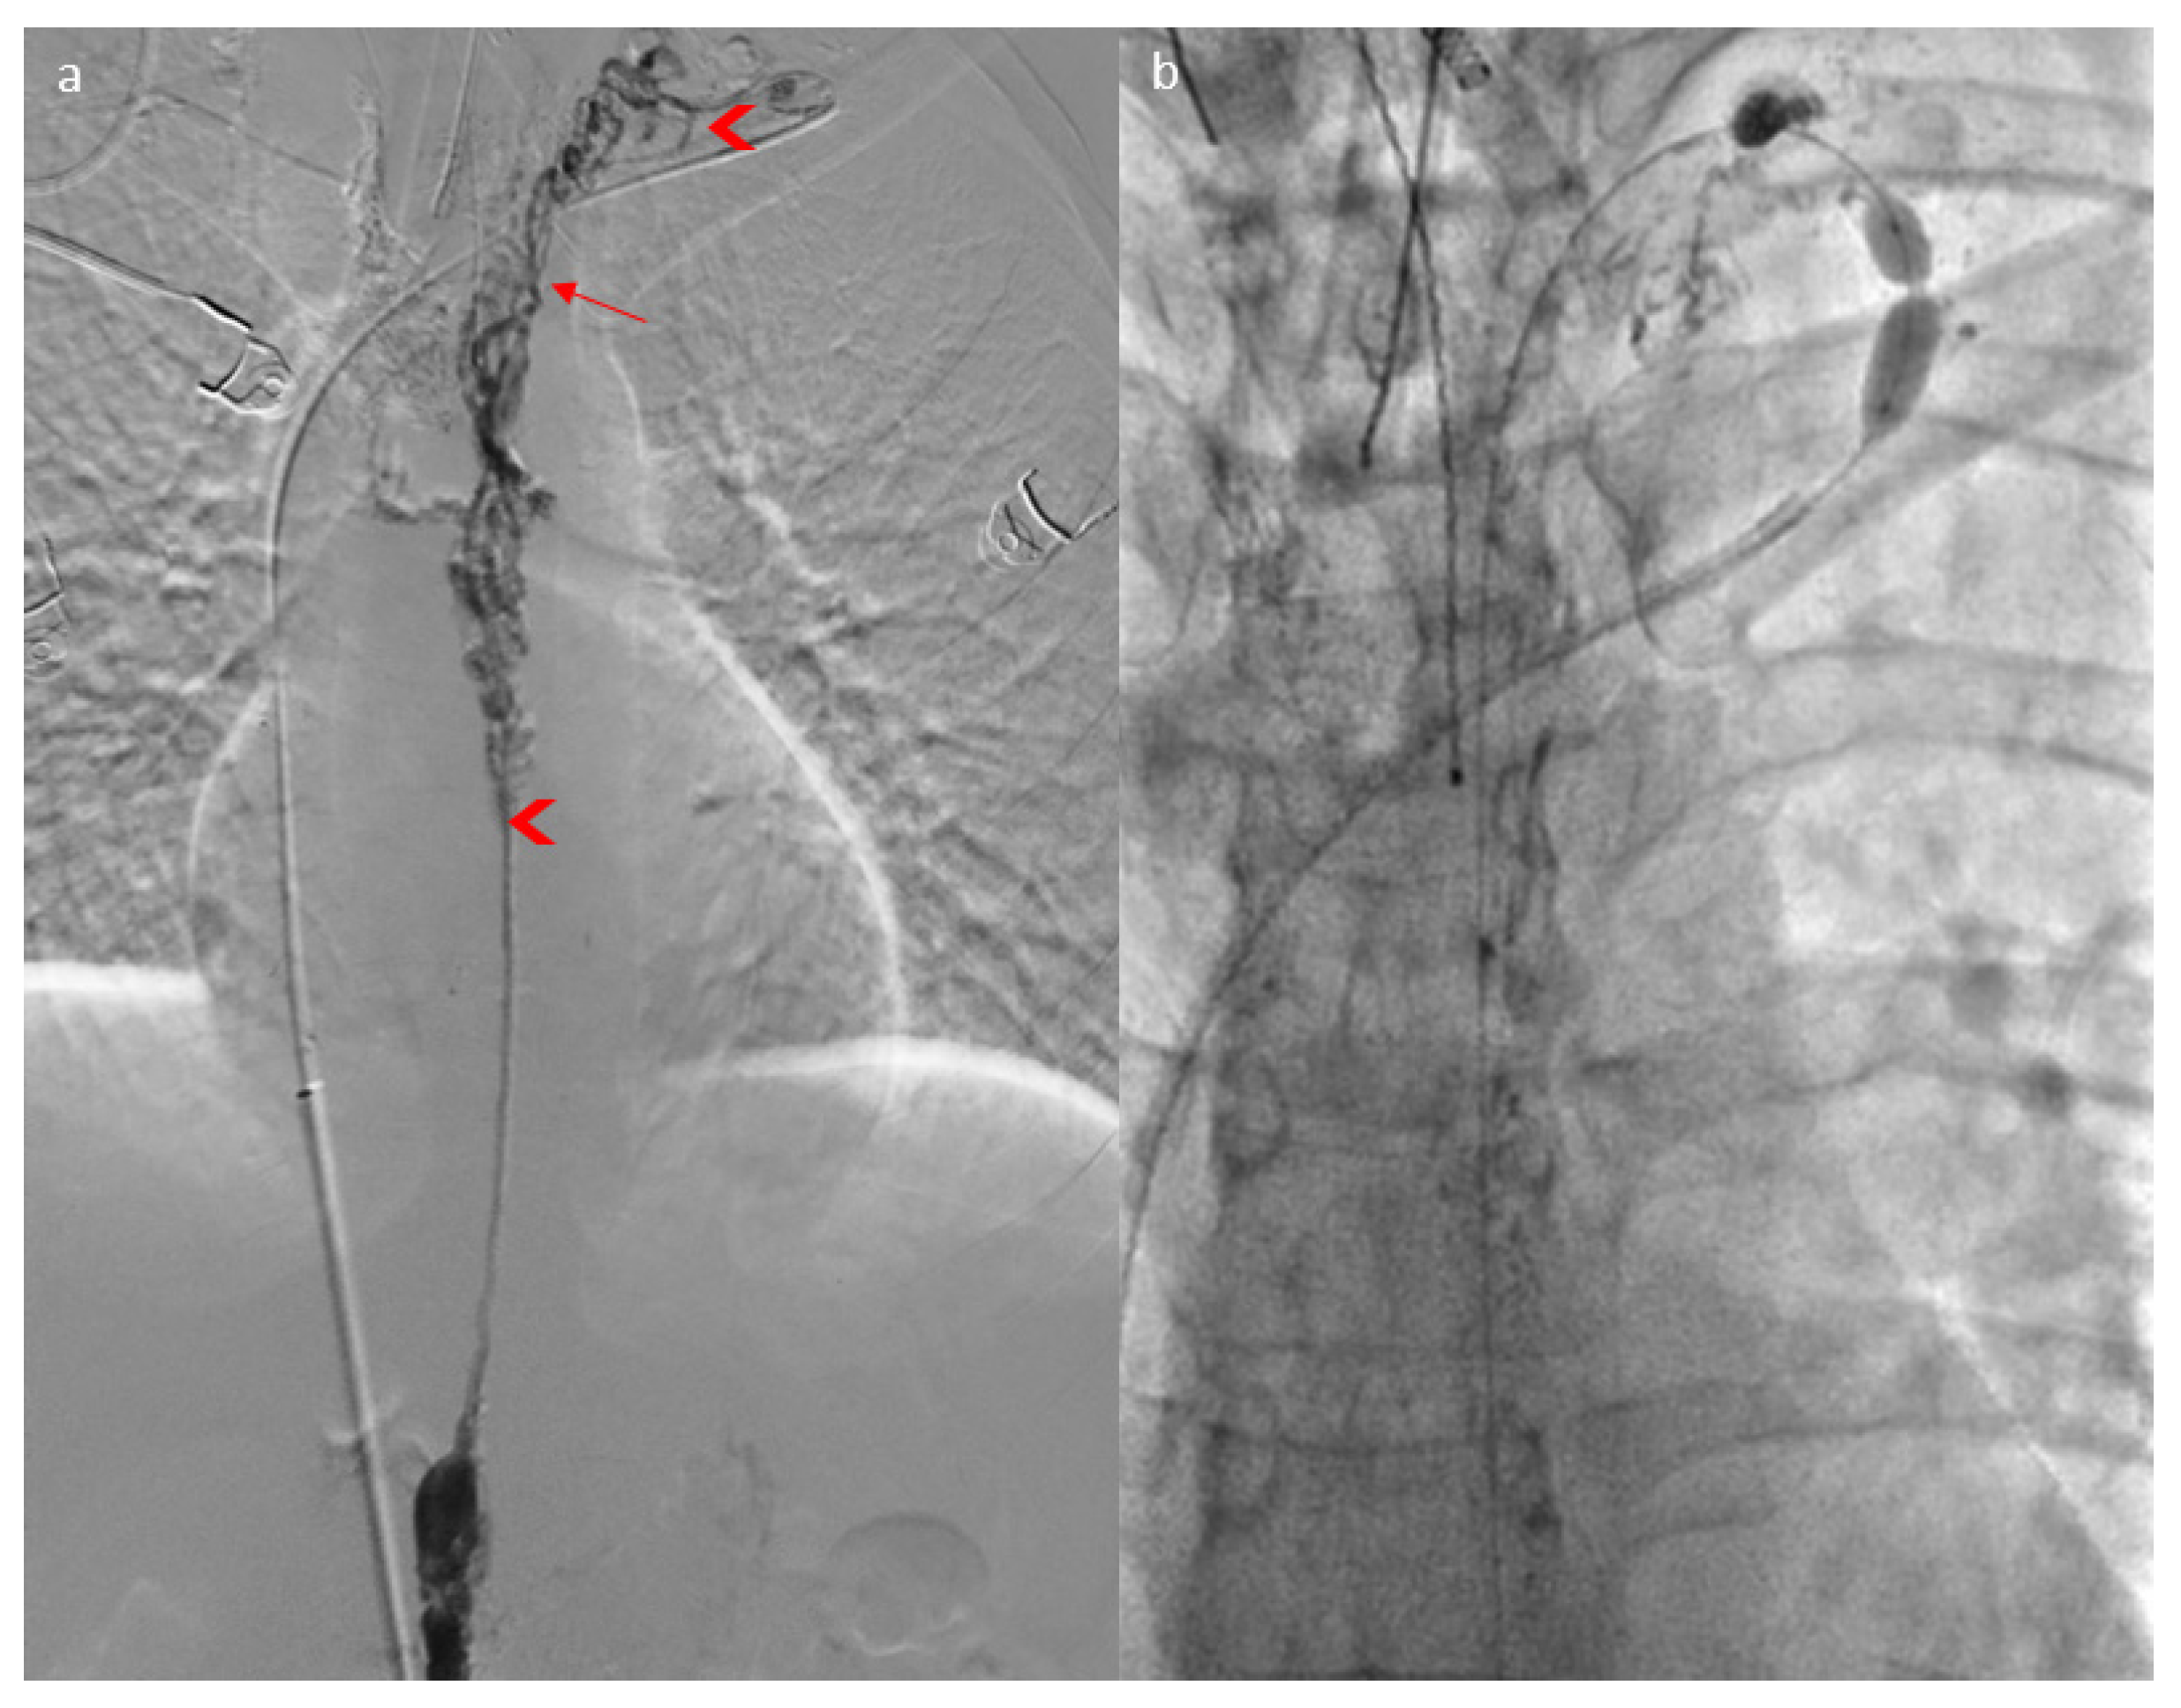

2. Case Report

3.2.3. Imaging